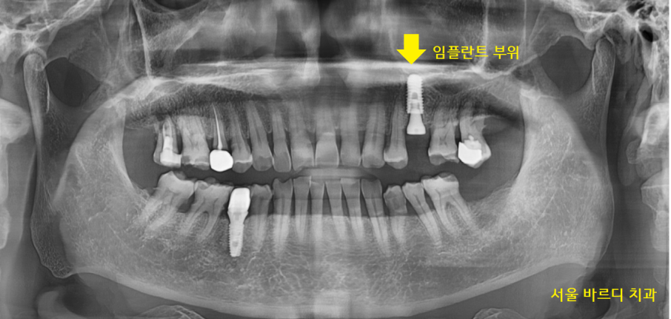

환자분께서 동의해 주셔서 임플란트 하는 쪽으로

설명을 드렸습니다.

강일동 치과에서 남아있는 치아를 발치

임플란트 치료를 하셨어요.

231211

진단도 ct로 놓치는 부분 없이

수술도 ct로 정확하게 진행합니다.

치아 부러짐 부위만 우선적으로 임플란트 수술하였습니다.